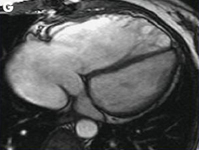

Magnetic resonance imaging (MRI) in a patient with pulmonary regurgitation following repair of tetralogy of Fallot. The patient has a restrictive right ventricle, and MRI shows decreased right ventricular volume

From: Chaturvedi RR, Redington AN. Heart. 2007 Jul;93(7):880-9; used with permission